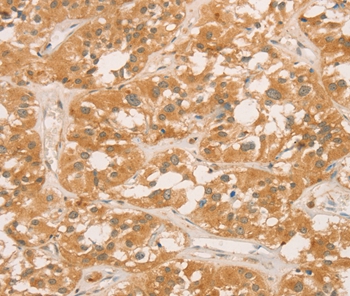

Immunohistochemical analysis of paraffin-embedded Human thyroid cancer tissue using #36365 at dilution 1/60.

Immunohistochemical analysis of paraffin-embedded Human gastric cancer tissue using #36365 at dilution 1/60.